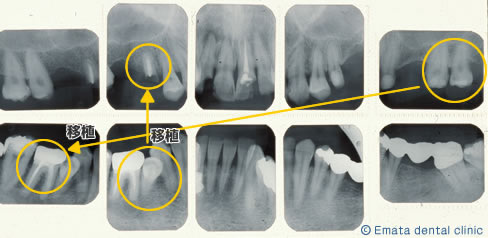

右上の虫歯が大きく、また右下の奥歯が根の病気が大きく抜歯になりました。 親知らずや内側に倒れた不必要になった歯があったので移植をおこないました。